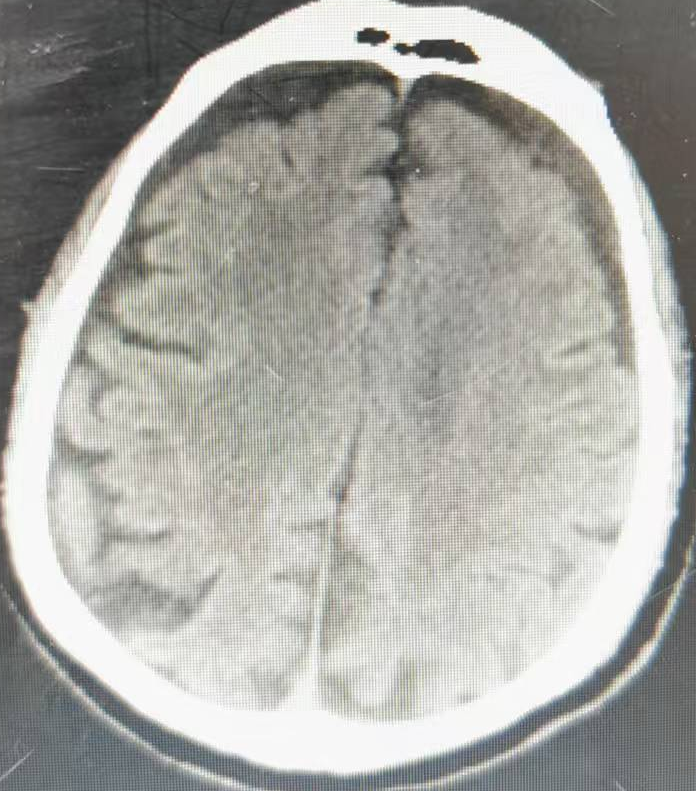

济阳区人民医院引进超高端准光子512层CT设备!检查更快、辐射更低、成像更准,在家门口就能享顶级影像诊断

近日,济阳区人民医院引进首台高端准光子512层CT设备,目前已全面完成安装调试并正式投入临床使用。此举标志着医院影像诊断技术迈入超高清、低剂量、全智能的新时代,将为济阳及周边地区百姓提供更精准、更安全、更...